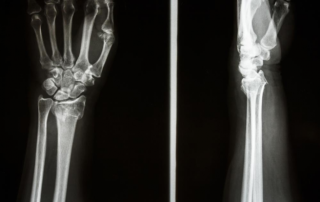

Fractures are a rather common occurrence in Canada. There is [...]